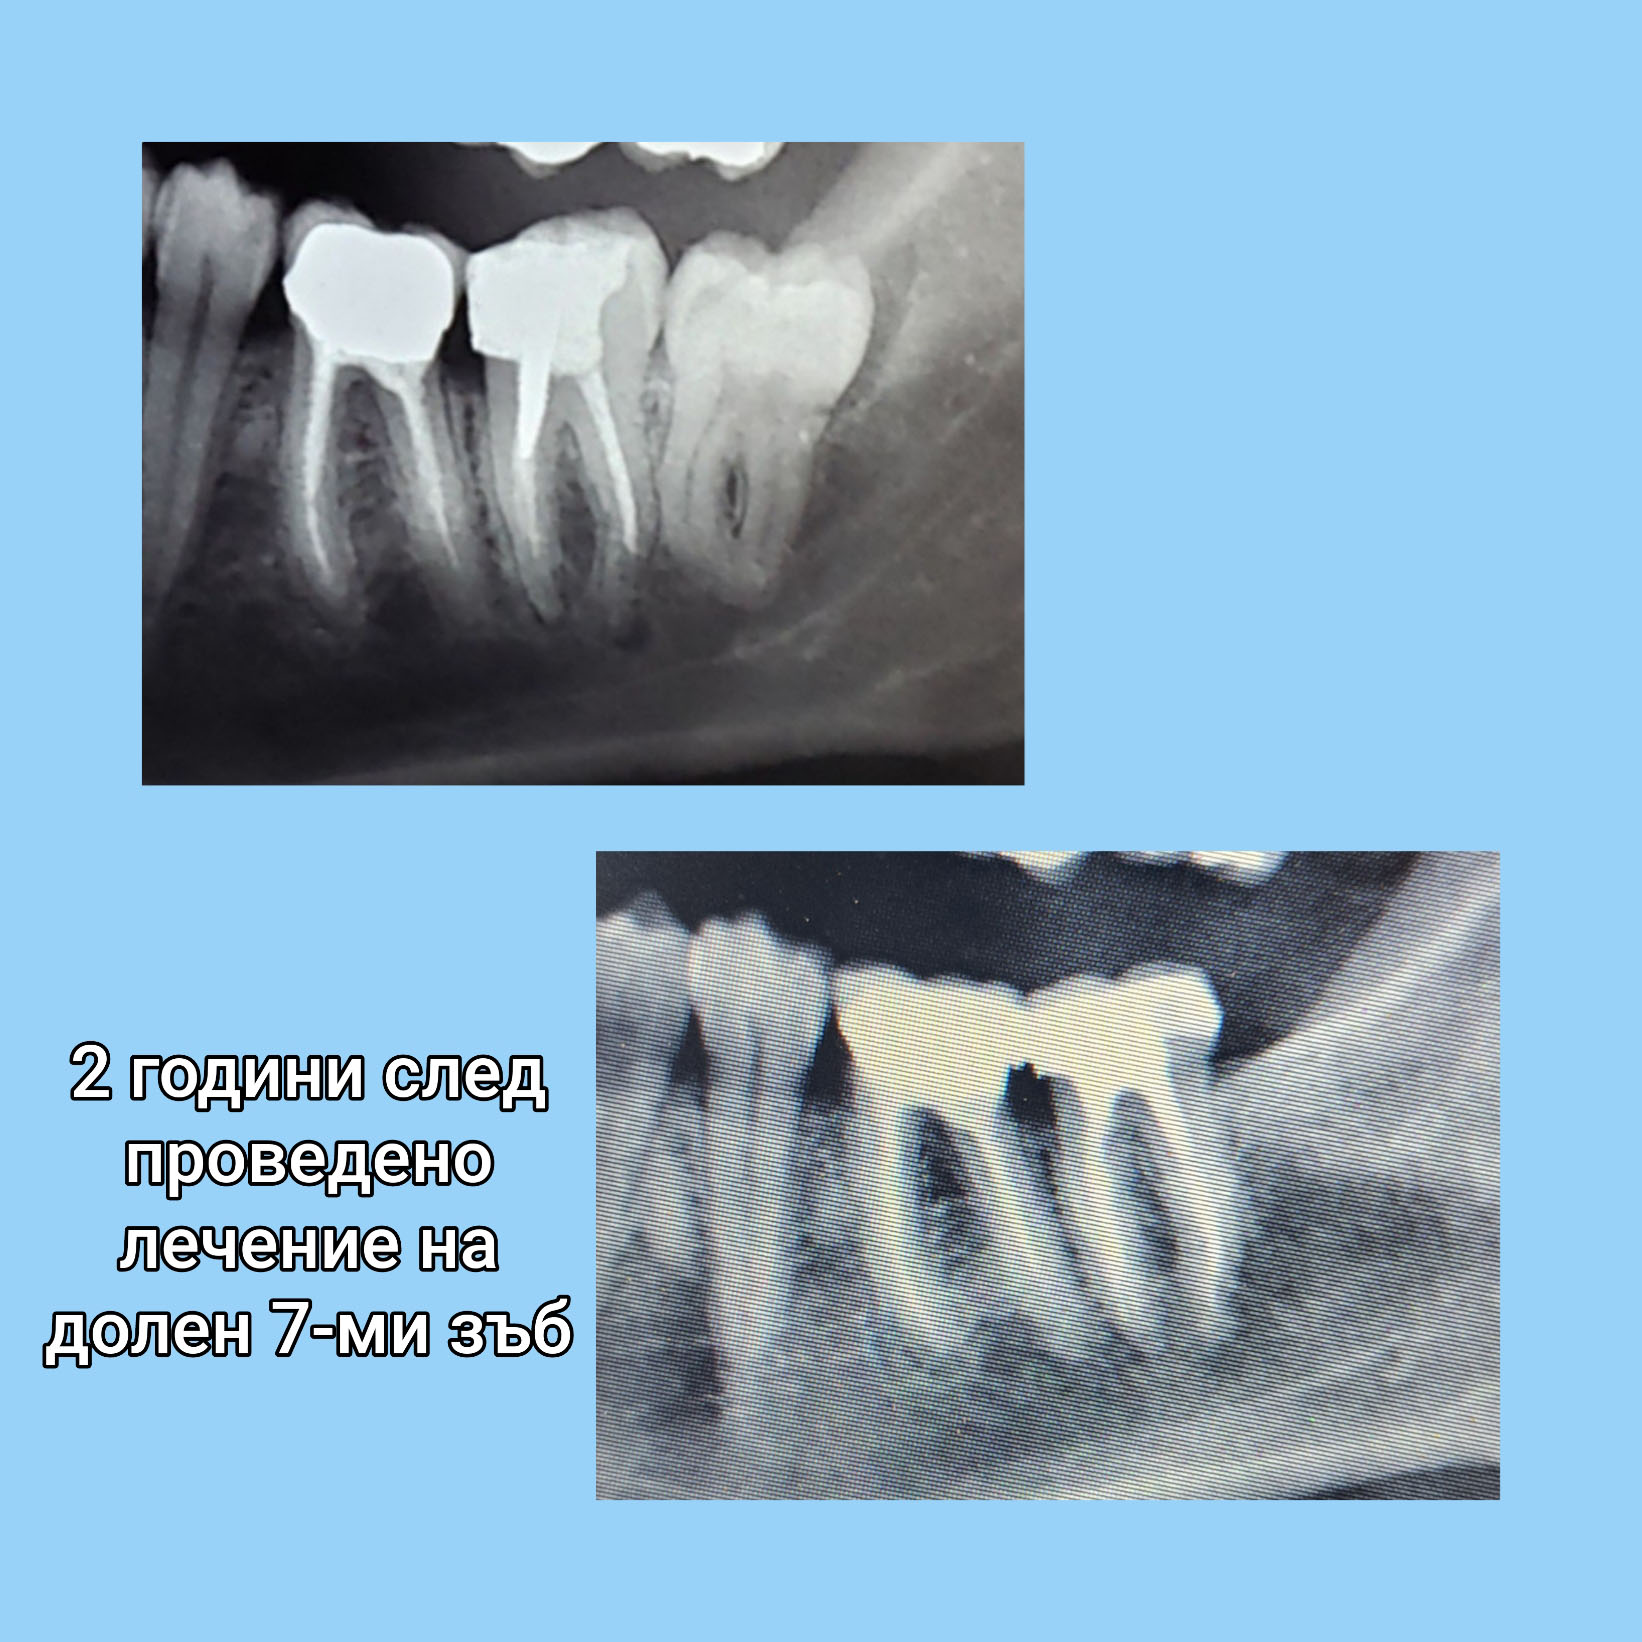

Пациент на възраст 35г. бе установено наличие на гранулом на зъб с безсимптомно протичане при направа на рентгенова снимка с цел екстракция на мъдрец. Лечението беше проведено в 3 посещения. Последната контролна снимка е направена 2 г. след лечението и се вижда пълно оздравяване на гранулома.